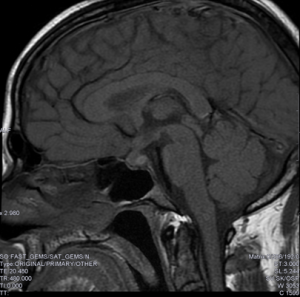

Explicación: Se requiere una RMN craneal para completar el estudio, puesto que esta nos puede proporcionar más información morfológica con respecto a la lesión, sobre todo con fines quirúrgicos.

En la prueba encuentras la siguiente imagen: